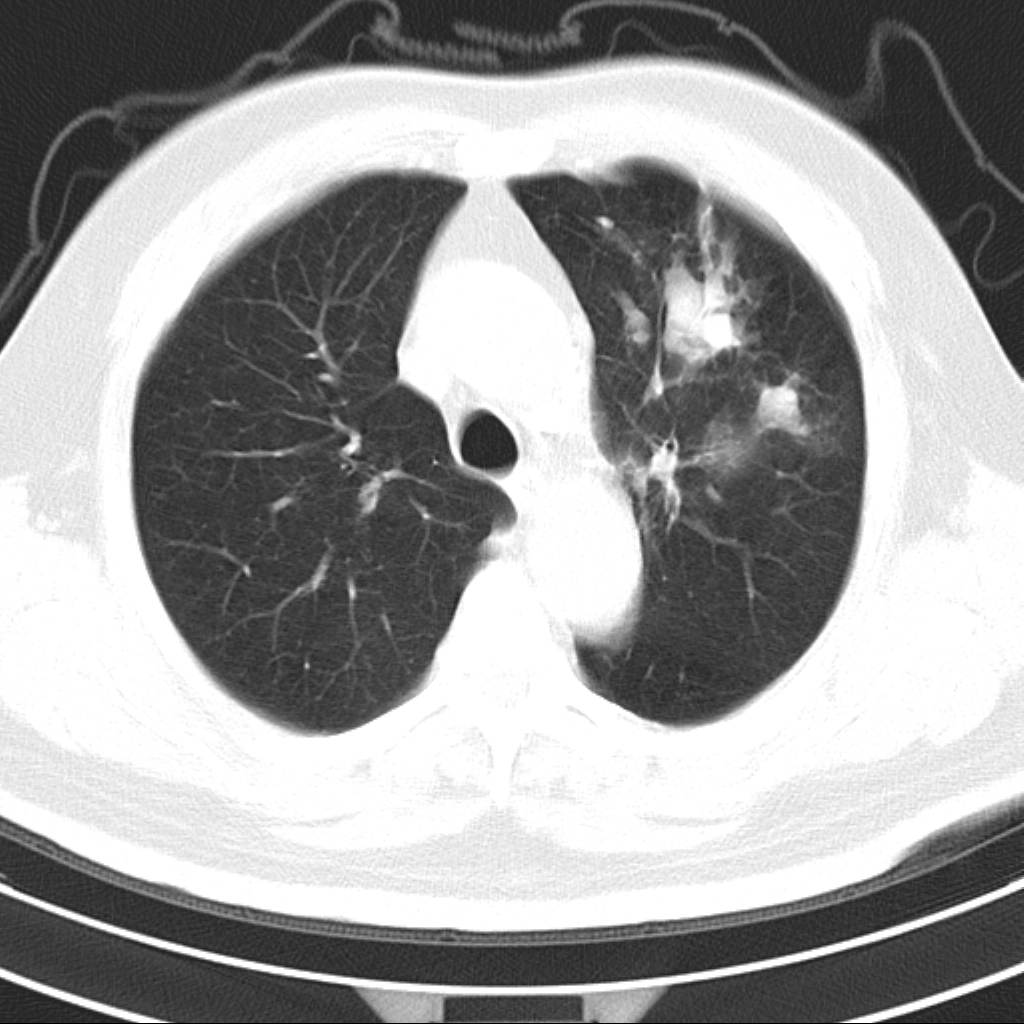

标题: CT18644:男,82岁,体检发现左肺阴影. [打印本页]

标题: CT18644:男,82岁,体检发现左肺阴影.

岁数太大,没有增强。麻烦见过的,给个诊断,顺便再说说病因

左侧中心型肺癌并粘液栓形成。很典型的。手套征。

支持 左肺上叶中央型肺癌并支气管内粘液栓形成。

尚不除外非感染炎症,过敏及哮喘曲霉菌病所致黏液栓塞,纸套征比较形象妾有一定特异性

考虑肺癌并左上肺阻塞性肺炎

支持 左肺上叶中央型肺癌并支气管内粘液栓形成,阻塞性肺炎